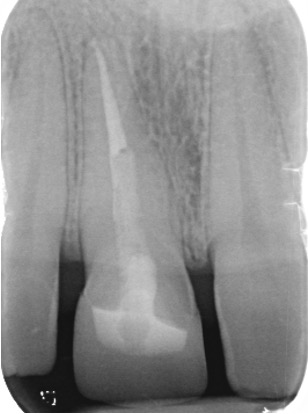

Secondary root canal treatment

Injury to the tooth can cause the root canal to shrink. High magnification and fine ultrasonic instruments are used to locate the root canal.

Fractured teeth

In this case a repeat root filling was completed. This is to minimise risk of infection from the exposed existing root filling. A fibre post and core was placed to build up the tooth sufficiently to retain a crown. This was then restored with an all ceramic crown. If there is insufficient tooth structure sometimes surgery can be carried out. In other cases it may not be possible to restore the tooth.